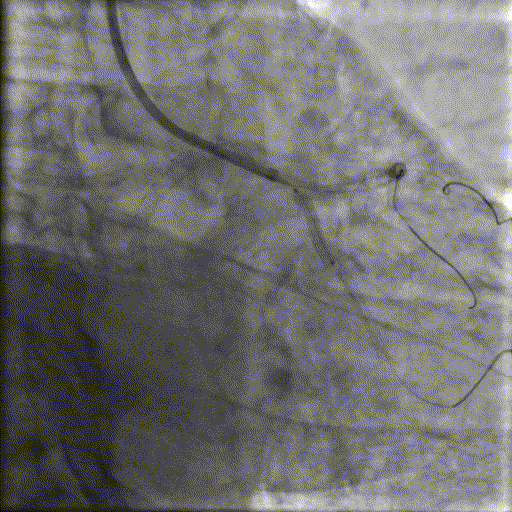

基础造影

右冠状动脉近段原有支架通畅,右冠一后降支细小,开口次全闭塞;左主干狭窄20%;前降支弥漫性病变,近段于间隔支形成分叉病交,最窄可见90%左右狭窄;回旋支近段70%,远段弥漫性病变,最重95%,远段可见侧枝向PDA远段供血。

手术过程

导丝到位

当指引导管冠脉开口到位后,选择三根对应导丝分别送入LCX、OM1、OM2远端。

OM2优先处理:

球囊预扩

当导丝通过病变后其他器械无法通过病变,此时选择不同尺寸的小球囊逐级预扩张病变,复查造影狭窄减轻不明显。为了解血管真实情况,遂启用IVUS检查。

术前腔内影像学IVUS指导

IVUS提示血管可见钙化明显,为360°环形钙化。遂考虑启动IVL治疗。

冲击波球囊治疗

2.5*12mm@4atm 冠脉血管内冲击波导管反复进行4个周期治疗,复查造影提示狭窄减轻。

支架植入并后扩

于OM2-LCX远端植入一枚药物洗脱支架,经非顺应性球囊后扩张支架,复查造影提示支架贴壁良好,未见夹层、血肿。

OM1处理:

使用预扩球囊处理OM1病变。

于OM1病变处植入一枚药物洗脱支架,经非顺应性球囊后扩张支架,复查造影提示支架贴壁良好,未见夹层、血肿。

最终,于LCX中远段行FFR检测,结果为0.78。鉴于本次手术时间较长、造影剂用量饱和,且患者症状已有效缓解、血流状态稳定。经综合评估后,决定对残余病变实施择期处理。